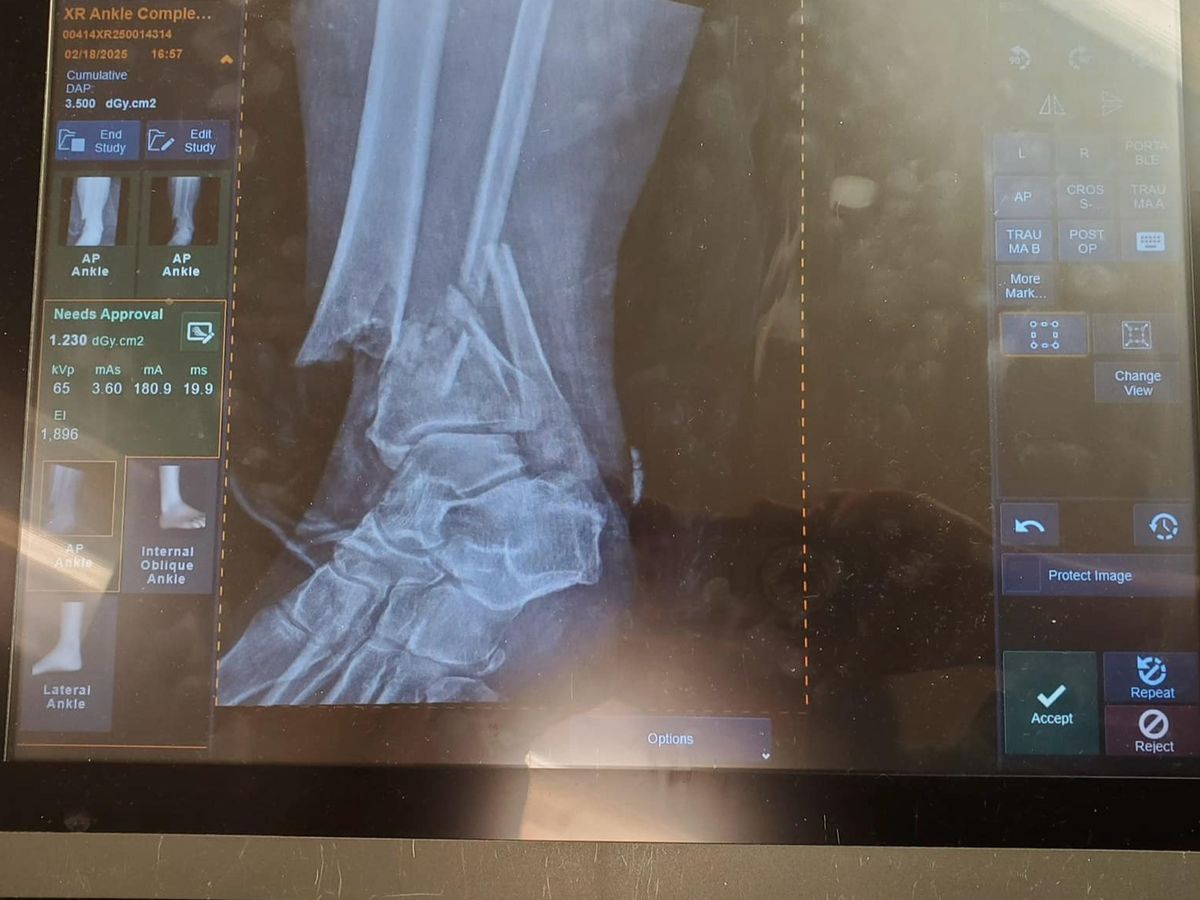

On February 12th, my close friend lost her job. Six days later, she broke her leg in a very, very bad way. She fractured both her tibia and fibula, injured her ankle joint, and the bone broke through the skin. It was a very serious, life-threatening situation. She has been in a trauma hospital to address the severity and set the leg to begin healing, moved to an assisted living facility while waiting for swelling to go down in order to have surgery to add hardware, back to the hospital for said surgery, and now to a rehab center.